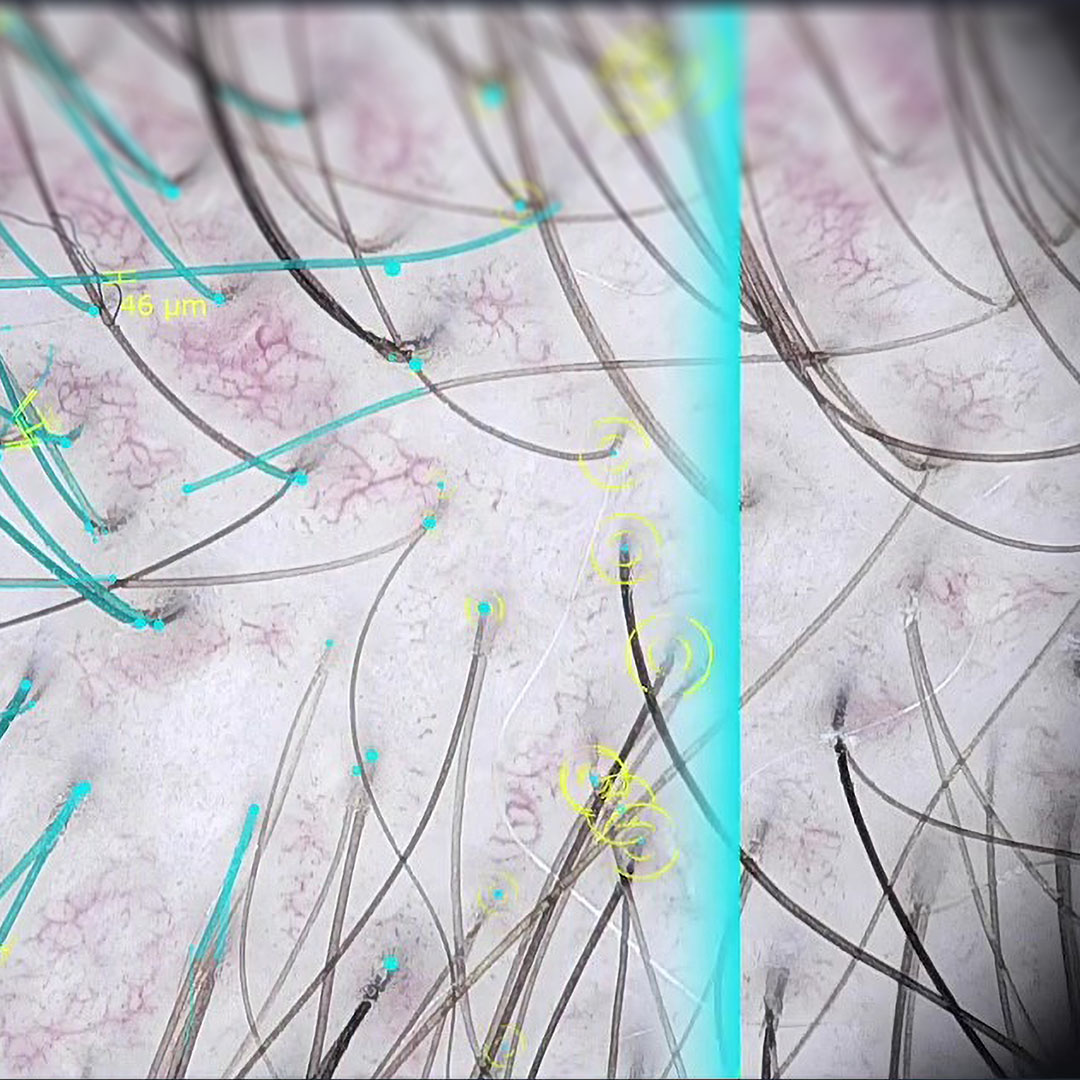

Haaranalyse und Trichos­­­kopie

Die Software Trichoscale DX unterstützt Sie bei der Evaluierung von Haar und Kopfhaut – schmerzfrei, ohne Zupfen und bei gekürztem oder ungekürztem Haar.

Das Programm berechnet gemessene Fläche, Anzahl, Dichte, durchschnittliche Länge, Anagen-Telogen-Rate sowie Anzahl und Dichte der Vellus- und Terminalhaare. Darüber hinaus liefert es Informationen zu Yellow Dots und follikulären Einheiten. Ein wertvolles Tool für die Haarsprechstunde!